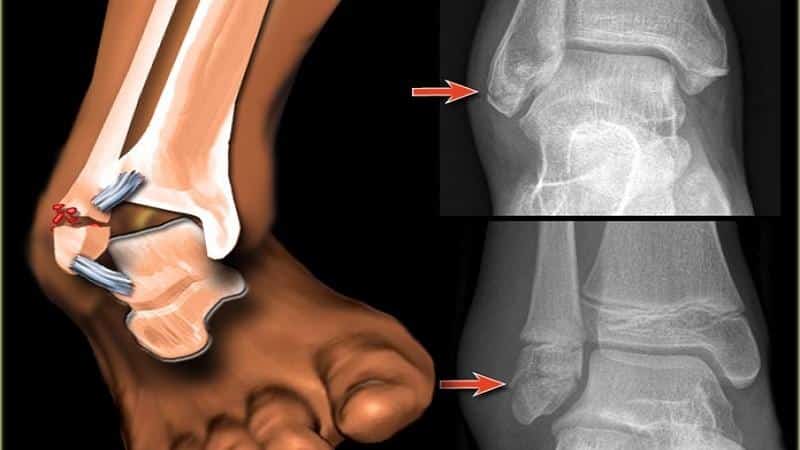

Для выбора тактики лечения назначается рентгенография голеностопного сустава в двух стандартных проекциях: боковой и переднезадней. На рентгеновских снимках выявляются линии переломов, их направление и степень смещения отломков, а также тип подвывиха и степень расхождения берцовых костей. В некоторых случаях может быть рекомендована компьютерная томография голеностопного сустава. Если требуется оценить состояние мягких тканей, проводят магнитно-резонансную томографию голеностопного сустава.